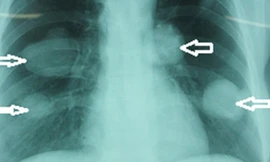

Lần đầu tiên Việt Nam phát hiện hai bệnh nhân bị sán chó. Hãi hùng hơn khi chúng tạo thành những khối u lớn, hàng nghìn đầu sán ngoe nguẩy trong phổi người “chực chờ” vỡ.